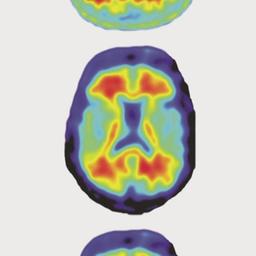

400.000 Menschen leiden in Deutschland an Parkinson, der zweithäufigsten neurodegenerativen Erkrankung nach Alzheimer. An neuen Medikamenten wird intensiv geforscht - mit positiven Ergebnissen. Von U. Till und M. Janning. mehr